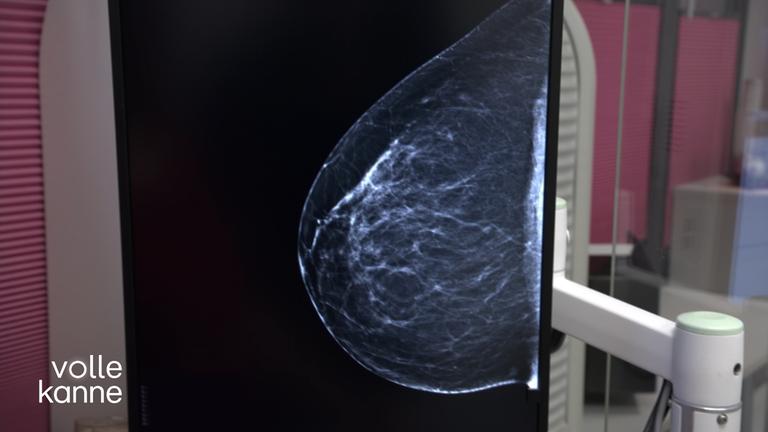

Josefine Preuß und Patrick Kalupa zu Gast. Außerdem: ePA – elektronische Patientenakte; Dr. Nice backstage; Colour-Drenching; Bräunungskapseln; Mammographie; Maisfrikadellen; Besserwisserin.